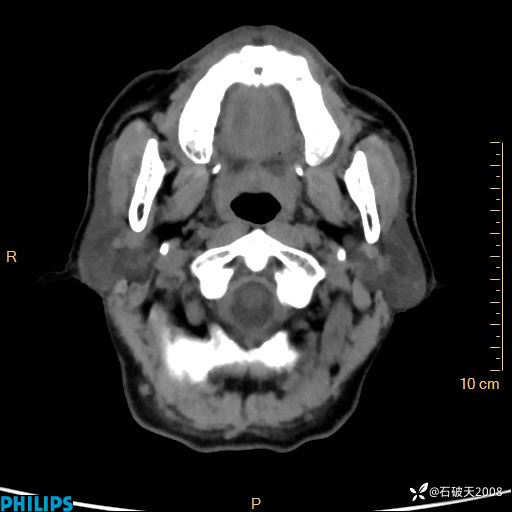

冠状位